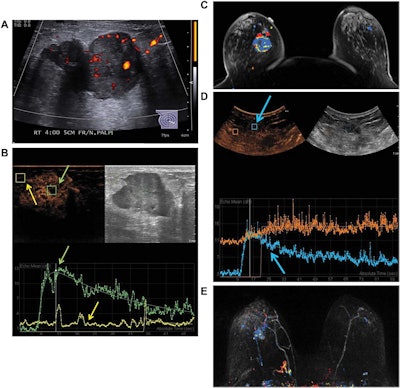

Images are from a 50-year-old woman presenting with a right breast lump that has biopsy-proven infiltrating ductal carcinoma. A: Targeted right-breast ultrasound imaging showed an oval hypoechoic mass with indistinct margins measuring up to 3.7 cm. B: At baseline before starting neoadjuvant chemotherapy, CEUS showed an avidly enhancing tumor (green arrows) with tumor peak intensity on the time-intensity curve generated by the Qlab software. The region of interest was placed on adjacent normal breast tissue (yellow arrows), which had a flat line on the time-intensity curve. The y-axis of the time-intensity graph corresponds to the intensity or mean echo (decibels), whereas the x-axis corresponds to the absolute time (seconds). C: Axial postcontrast fat-saturated MRI at baseline showed an enhancing tumor with mixed kinetics in the right breast. After neoadjuvant chemotherapy was completed but before surgery, contrast-enhanced and MRI scans were again performed. D: CEUS showed a 2-cm residual enhancing tumor with a time-intensity curve (blue arrows) that had rapid enhancement and washout. E: Maximum-intensity projection contrast-enhanced MRI performed after neoadjuvant chemotherapy was completed showed a decrease in the size of tumor to 2 cm with predominantly progressive kinetics. At the time of right lumpectomy, this patient had 1.5 cm of invasive tumor in the right breast, consistent with a noncomplete pathologic response. Both the contrast-enhanced ultrasound and MRI studies predicted that there would be noncomplete pathologic response at the time of surgery. Images courtesy of the Journal of Ultrasound in Medicine.

At baseline prior to treatment, contrast ultrasound and MRI both yielded a 3.1-cm median tumor size; the modalities had strong correlation (r = 0.88, p < 0.001) in tumor size measurements. The researchers noted that one patient had a deep tumor that did not enhance on baseline CEUS, but it was visible on conventional ultrasound and displayed subthreshold enhancement on MRI.

After neoadjuvant chemotherapy, agreement on tumor size dropped (r = 0.66, p = 0.004) but was still comparable. The researchers observed, however, that in a subset of 15 patients who had both CEUS and MRI studies that could be compared with tumor size at surgery, CEUS (r = 0.75, p < 0.001) correlated better with tumor size at surgery than MRI did (r = 0.42, p = 0.095).

In addition, contrast ultrasound and MRI were equally effective in predicting pathologic response to treatment. The modalities both accurately predicted three (75%) of the four patients who had a complete pathologic response, and eight (72.7%) of the 11 patients with a noncomplete pathological response.